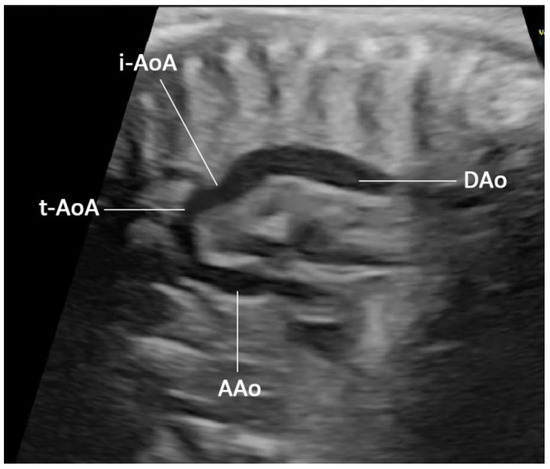

2. Case Presentation